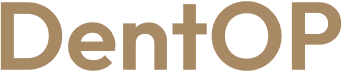

La 24h de la procedura ,,Dantură Fixă în 24h pe implanturi dentare”, domnul S. a primit primele lucrări provizorii pe care le-a purtat timp de 6 luni. S-a prezentat la controalele periodice și a respectat cu strictețe indicațiile și astfel s-a putut vindeca rapid și eficient.

Alături de sfatul Medicului Protetician, pacientul a ales dantura potrivită pentru fizionomia și trăsăturile sale. Astfel în doar 24h a putut mânca și zâmbi, iar acum are o dantură impecabilă care îl ajută să aibă încredere în zâmbetul său.

Se bucură acum de un zâmbet frumos și sănătos pe care l-a obținut în scurt timp cu ajutorul implanturilor dentare.